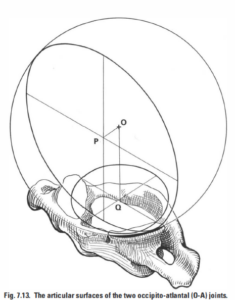

頭痛とめまいを引き起こした頭蓋頸椎の変位